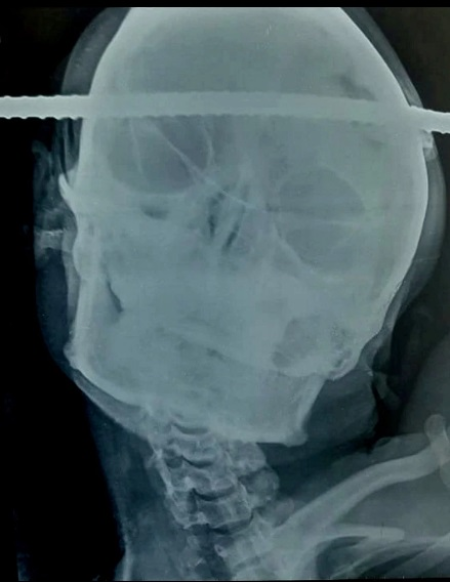

A 21-year-old man has shocked the world by surviving after iron rod pierced through his head.

A man has lived after a steel rod speared through his head. The sad incident happened after he fell down a well. The construction worker identified as Sanjay Bahe, 21, was doing some repair work at a construction site in Balaghat, India when he fell. He was rushed to B.J Hospital after the iron rod pierced him from the right temporal region of his brain to the left frontal region. At hospital, medics reported that Sanjay’s blood pressure suddenly dropped. So the team led by Dr Pramod Giri began a 90-minute surgery in a bid to remove the rod. Sanjay was resuscitated with blood and blood products and was taken for surgery at the Neuron Hospital. Miraculously, the rod was removed safely with hardly any bleeding or injury to the surrounding area. Dr Giri said Sanjay’s main venous sinus to the brain was preserved by just millimetres.